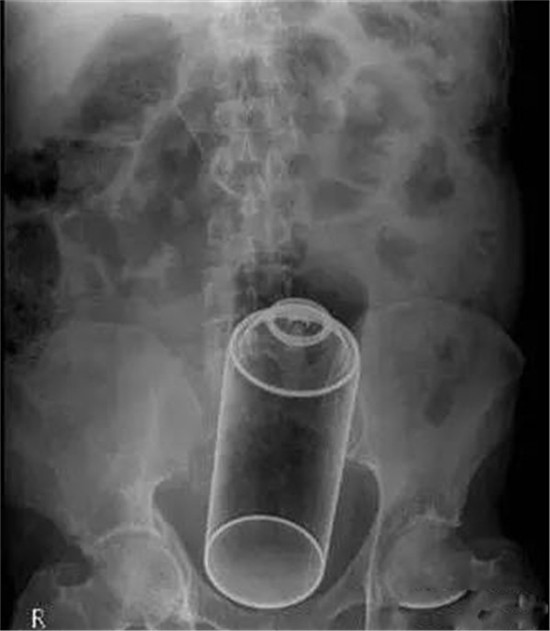

速溶咖啡的罐子。

来电池了。

一节一号电池。

医生给他检查的时候,发现已经有腹膜炎症状,怀疑肠梗阻,拍了个片子,就是上面那个片子:一条大黄鳝在肚子里。

考虑到他已经有腹膜炎的症状,说明肠子已经有个地方破了。只能动手术了。

把肚子打开后,发现大肠破了个洞,黄鳝的头,就在那个洞里。他肚子里都是大便。他的肠子水肿很厉害。黄鳝堵住了大肠,肠梗阻,导致大肠坏死穿孔了。

这种情况下,就是把大肠的洞补起来,洞也长不好。只能造瘘了。也就是在破了个洞的地方把大肠割断,肚皮上挖个洞,大肠拖到肚皮外面,以后的大便从肚皮上排出来。等肚子里炎症消退后,再把大肠放回肚子里接回去。这样他要动2次手术。

就这样,他死里逃生了。